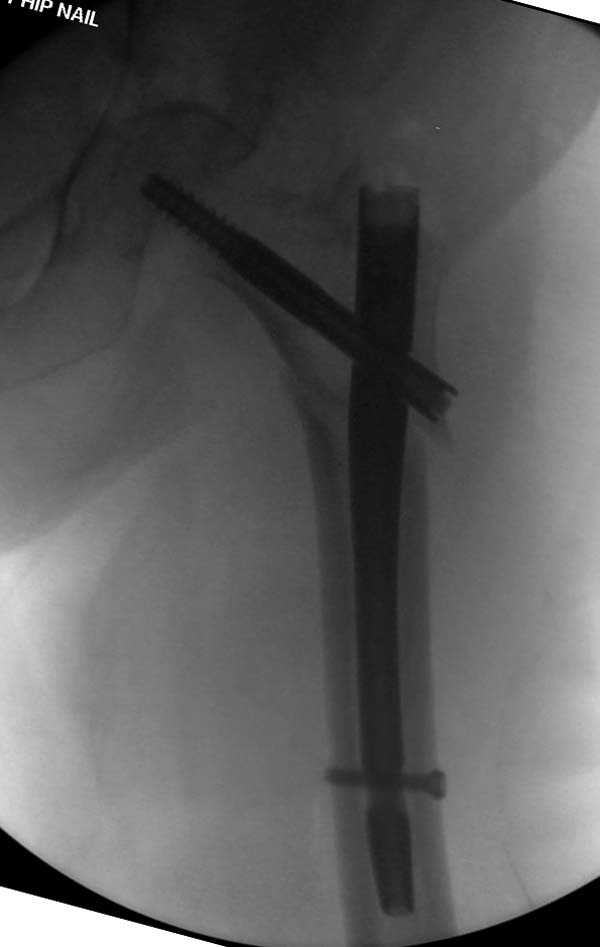

Здесь представлен случай, где в послеоперационном периоде обнаружена техническая ошибка, Gamma 3 установлен с нарушением методики. Больная в 91 лет, прооперирована через день после поступления и выписана через 48 часов.

При первом послеоперационном поликлиническом осмотре больная предъявила жалобы на боли в бедре. В серийных снимках обнаружен продольный перелом верхнего отдела бедра.

Считаем, что техническая ошибка произошла во время установки гвоздя, когда рассверливанию канала не уделили должного внимания. Канал остался узковат, и гвоздь был забит с силой. Полная нагрузка конечности приостановлена на две недели, и боли в конечности изчезли. Больная начала нагрузку и перелом срастается.-- Djoldas Kuldjanov, M.D.Associate ProfessorDepartment of Orthopedic SurgerySt. Louis University

Мне думается, что варусное положение проксимального отломка на последующих снимках не более чем проекционный феномен. Раскол же диафиза вдоль, наверняка, связан с чрезмерно насильственным введением штифта. Вообще, при реверсивных, да и обычных вертельных переломах, многие давно отказались от короткой Гаммы в пользу long-версии. Но в любом случае надо быть на 100 уверенным в подготовке канала.

Перелом А3, подвертельный, вероятно, на длинной версии гвоздя такого бы не произошло

eto nestabil'nui perelom. nado bylo stavit' gamma long. kanal uzkii (bylo vidno). mesiaz ne nagrujat', vse srastetsia!